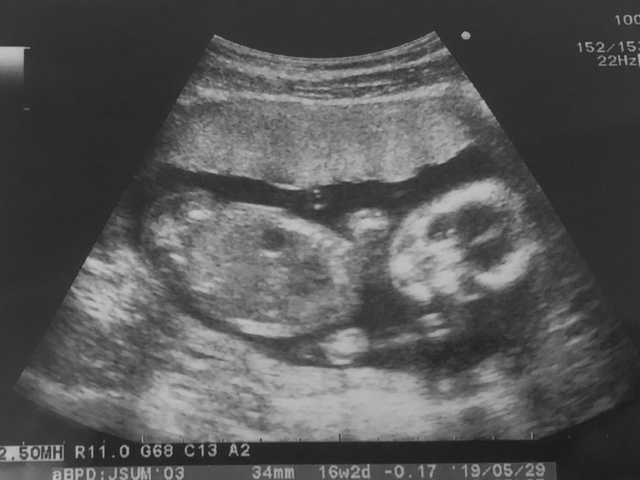

15週6日(15w6d・男の子・双子)|maiiii さん(17歳)

エコー写真撮影時のエピソード:

初めての妊娠。産婦人科に行くと双子ですと言われ、義母さんは信じられないと、もう一回検診しに行きました。やっぱり双子。親戚に双子は居なくてみんな驚きました。

産んでいいって言われてこれからの話し合いをして、毎回の検診には義母さんがついてきてくれました。双子は管理入院もなく、2人とも2キロ越えで立派に生まれてきました。